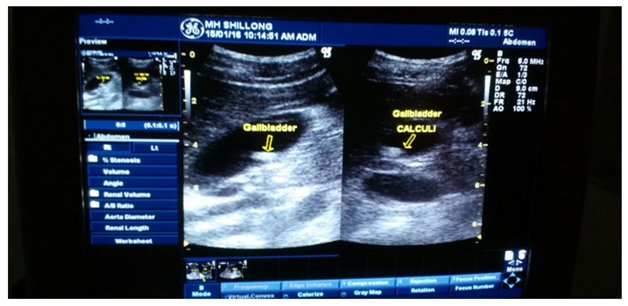

A 8year old girl born to non consanguineous marriage reported to the outpatient department (OPD) with history of acute pain abdomen of 3days duration, speech delay, global developmental delay and squint since birth. She was born at 37weeks of gestation by emergency Lower segment caesarean section LSCS (Indication fetal distress) with birth weight 2.25kg, length 45cm and head circumference 34cm. The baby cried immediately after birth and was started on breast feeds within 4hrs of birth. There were no antenatal risk factors. The initial milestones was delayed (cognitive more than motor). There was history of recurrent lower respiratory tract infection since 2yrs of age which required frequent hospital admission and antibiotics. She developed seizure at 5yrs of age which was managed with anticonvulsant. The MRI (Brain) done at this stage revealed small foci of hyperintensity in T2 weighted image in frontal and parietal region. The EEG was normal. There was no family history of any chromosomal disorder. She was the eldest sibling and other siblings were 3 and 5years old normal for age. Presently she was brought with history of acute abdomen pain on right upper abdomen which was colicky associated with fever with chills and vomiting. The clinical evaluation revealed weight 21kg (5th P) and height 120cm (3rd P) and head circumference 51cm. The Dysmorphic features were doliocephalic head, hypertelorism, Squint, flat bridge of nose, high arched palate, wide spaced nipple, prominent forehead and microcornea on right side and everted umbilicus (Figure 1A & 1B). The vital parameter revealed temperature 102degree Farenheit with pulse 110/min, respiratory rate 30/min, blood pressure 110/70mm Hg. The abdominal examination revealed marked tenderness over right hypochondriac region and other system was essentially normal. She was immediately admitted and was started on IV fluids and antibiotics and sample was sent for complete blood count, biochemistry and was planned for sonography of abdomen. The investigation revealed polymorpho lecucocytosis with normal biochemistry with positive CRP. The thyroid profile was normal. The ultrasonography revealed multiple Gall bladder calculi with largest measuring 18mmx 19mm (Figure 2). The gall bladder was distended and Common bile duct (CBD) was normal. The lipid profile was normal. The Chest radiograph was normal. She was managed with antibiotics and IV fluids and she responded well to conservative management. The Karyotyping (Figure 3) was done in view of dysmorphism and developmental delay which revealed monosomy 18 with translocation 13p 11/18 which was later confirmed by FISH. The hearing assessment test was normal. The Eye evaluation revealed concomitant squint. The Intelligent quotient test revealed score of 60. She was planned for speech therapy and was kept under follow up.

Figure 2 Ultrasonography of abdomen showing gall bladder stone with post acoustic shadow.